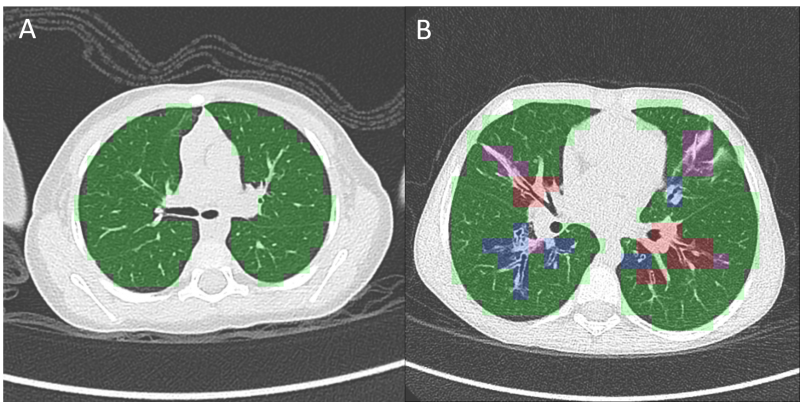

CT scan of (A) a patient with normal lungs and (B) a patient with severe cystic fibrosis, analyzed with PRAGMA-CF. This analysis quantifies disease patterns related to CF, including normal lung tissue (green), bronchiectasis (blue), airway thickening (red) and mucous plugging (pink). Thirona is developing an automated AI solution to quickly and accurately quantify PRAGMA-CF disease patterns.